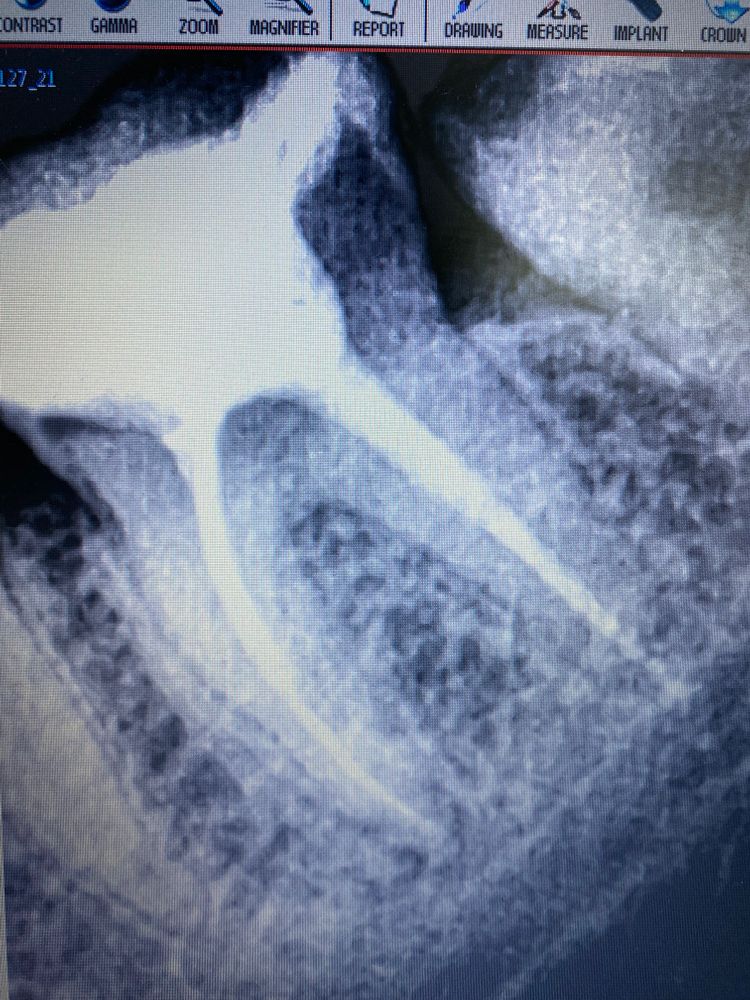

Kristina 4 года Сделали зуб не болит, но сделала снимок не видно , должна ли быть пломба до конца корня, или все пра Посмотрите еще 20 записей на эту тему Отменить Ответить Kristina 14.02.2022 Ответить Мария Мария Kristina, а стоматолог что сказала? 14.02.2022 Ответить У сына аллергия после года жуткая вылезла Ребёнок прыгает на одном месте Чаты Беременных Выберите чат: Январята-2026 Февралята-2026 Мартята-2026 Апрелята-2026 Майчата-2026 Июнята-2026 Июлята-2026 Августята-2026